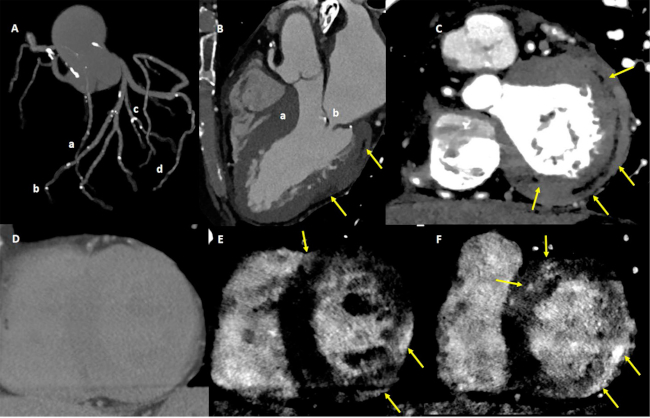

Caso 2. Se trata de un paciente de 57 años, con diabetes tipo 2 e hipertensión. Ingresó con diplopía y cefalea del despertar, con inestabilidad de la marcha de inicio incierto (NIHSS: 0). La presión arterial al ingreso fue de 170/100 mmHg, con valores de troponina normales. En la RM de encéfalo con angioRM se evidenció isquemia aguda de fosa posterior sin oclusión a nivel de los vasos explorados. Evolucionó con mejora completa de su sintomatología. Se realizó una TC espectral cardíaca (Figura 2) para evaluar la etiología del ACVi, y se observó hipertrofia asimétrica del VI a predominio septal, áreas de infiltración grasa intramiocárdica de patrón lineal a nivel inferolateralbasal, y RT de patrón predominantemente intramiocárdico a nivel inferolateral medio, y parches intramiocárdicos a nivel anterolateral basal, con función sistólica conservada. Además, se identificó ateromatosis multifocal a predominio de lesiones de pequeños vasos y engrosamiento valvular no acorde con la edad. Se calculó un VEC septal de 40%, y un VEC de 70% a nivel del área lateral con máximo realce. Esos hallazgos se interpretaron como miocardiopatía de etiología no isquémico-necrótica, que podían corresponder a miocardiopatía arritmogénica dominante izquierda con componente de hipertrofia. Sin embargo, si bien es poco probable, debido a que la función sistólica se encontraba conservada, no se descarta la posibilidad de cardiotoxicidad vinculada con con antecedente de quimioterapia debido a la presencia concomitante de lesiones coronarias, valvulares y miocárdicas en un paciente relativamente joven.